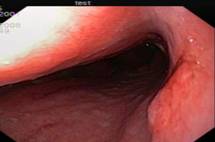

Распространенный рак желудка. Во II группе при визуальном осмотре 282 пациентов диагностирован распространенный рак желудка и согласно классификации указана его макроскопическая форма. У всех больных рак был подтвержден морфологически, причем дифференцированные аденокарциномы были у ,9%) пациентов, низкодифференцированные – у ,1%).Общий эндосонографический критерий всех форм распространенного РЖ – это наличие неоднородного гипоэхогенного образования, которое исходит из слизистой оболочки, с глубиной инвазии в мышечный или серозный слой, или выходит за пределы стенки желудка, с нарушением дифференцировки между слоями (рис.2).

Рис.2. 71 год. Блюдцеобразный рак нижней трети тела желудка.

Гистология – умереннодифференцированная аденокарцинома:

а - визуальная картина блюдцеобразного рака; б - эндосонограмма блюдцеобразного рака, гипоэхогенное образование с инвазией в серозную оболочку.